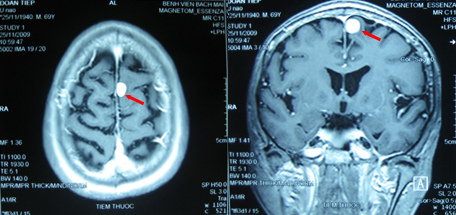

Thông qua xét nghiệm dịch não tủy, bác sĩ có thể biết được loại viêm màng não mà trẻ đang mắc phải. - Chụp CT, MRI hoặc chụp X-quang được thực hiện khi trẻ có biểu hiện tăng áp lực nội sọ (ICP) hoặc xuất hiện các hiệu ứng khối (thần kinh khu trú, phù gai thị, co giật, mất ý thức, nhiễm HIV hoặc suy giảm hệ miễn dịch).